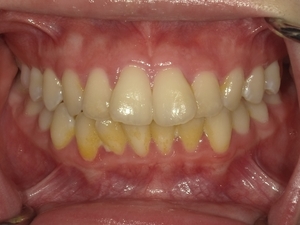

ガタガタとした歯並びや八重歯(叢生)CASE72